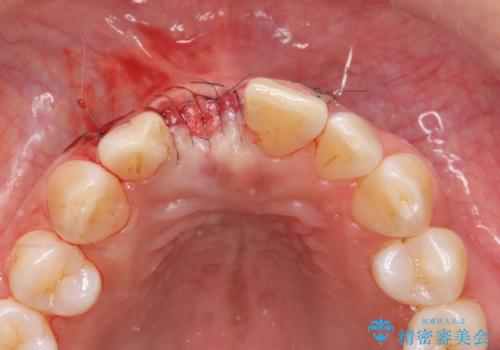

審美的・機能的に良好な位置に埋入するには、骨量が十分ではなかったため骨の造成を併用したインプラント埋入外科手術を行います。

前歯のインプラントを審美的に仕上げるには、インプラント周囲に十分な骨の量と厚みのある歯肉、そして埋入位置の精密な位置付けが重要です。